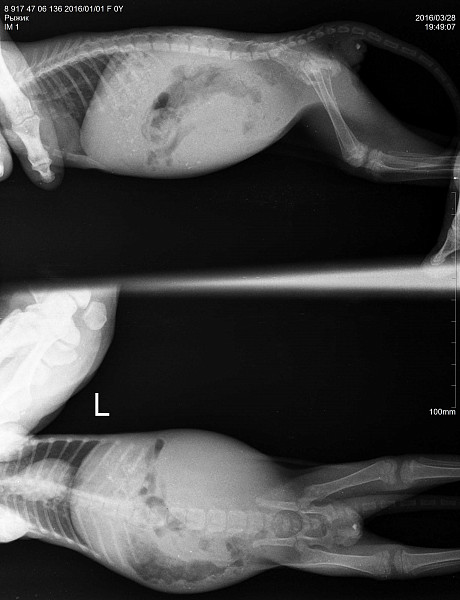

Заболевания позвоночника у домашних животных: диагностика и лечение

Раздел: Визуальные истории